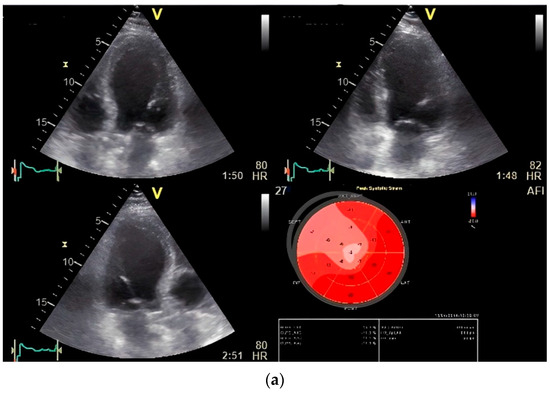

The results of our study revealed a favorable correlation between strain measurements obtained via 2D speckle tracking, both at rest and under stress, and the identification of significant coronary artery disease as confirmed by invasive coronary angiography. The strain parameters exhibited greater sensitivity and specificity during stress testing in comparison to resting states. Importantly, the ST fluctuation rate measured through magnetocardiography showed the highest level of sensitivity (Figure 5).

Figure 5.

(a) Global longitudinal strain (GLS) by speckle tracking at rest showing decreased strain in septal region. (b) GLS by speckle tracking under stress (first phase stress at 20 mg/kg/min intravenous infusion of dobutamine) of the same patient showing decreased strain distributed over anterior and anterolateral region (significant left circumflex stenosis was revealed in coronary angiography). (c) Disturbance of T wave dispersion at stress in the same patient.